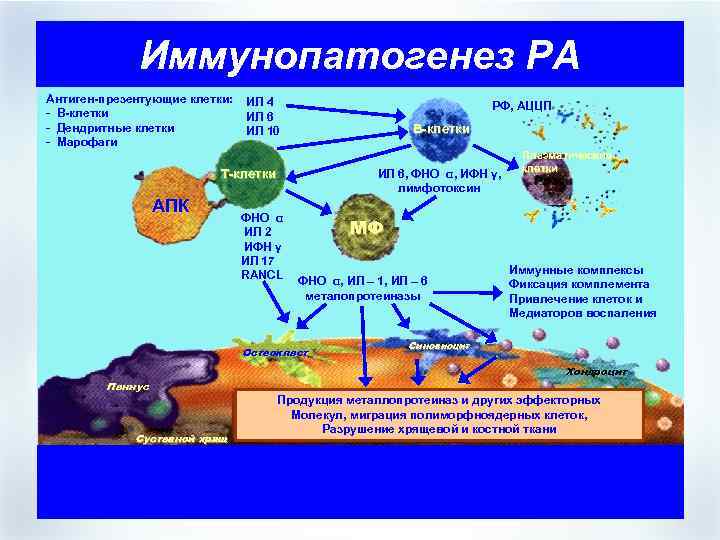

Иммунопатогенез РА Антиген-презентующие клетки: - В-клетки - Дендритные клетки - Марофаги ИЛ 4 ИЛ 6 ИЛ 10 РФ, АЦЦП В-клетки ИЛ 6, ФНО α, ИФН γ, лимфотоксин Т-клетки АПК ФНО α ИЛ 2 ИФН γ ИЛ 17 RANCL МФ ФНО α, ИЛ – 1, ИЛ – 6 металопротеиназы Остеокласт Паннус Суставной хрящ Плазматические клетки Иммунные комплексы Фиксация комплемента Привлечение клеток и Медиаторов воспаления Синовиоцит Хондроцит Продукция металлопротеиназ и других эффекторных Молекул, миграция полиморфноядерных клеток, Разрушение хрящевой и костной ткани

Иммунопатогенез РА Антиген-презентующие клетки: - В-клетки - Дендритные клетки - Марофаги ИЛ 4 ИЛ 6 ИЛ 10 РФ, АЦЦП В-клетки ИЛ 6, ФНО α, ИФН γ, лимфотоксин Т-клетки АПК ФНО α ИЛ 2 ИФН γ ИЛ 17 RANCL МФ ФНО α, ИЛ – 1, ИЛ – 6 металопротеиназы Остеокласт Паннус Суставной хрящ Плазматические клетки Иммунные комплексы Фиксация комплемента Привлечение клеток и Медиаторов воспаления Синовиоцит Хондроцит Продукция металлопротеиназ и других эффекторных Молекул, миграция полиморфноядерных клеток, Разрушение хрящевой и костной ткани